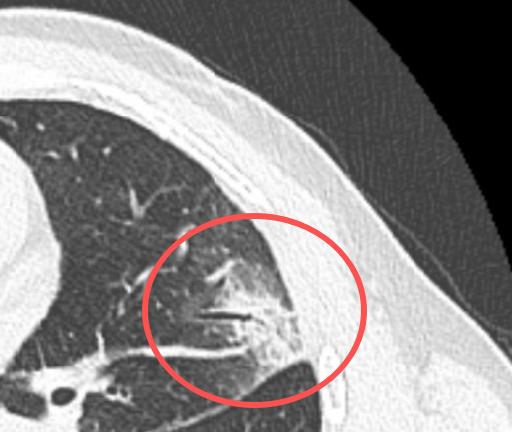

换了药后,肺结节就消失了!44岁的男性,在今年4月底查出肺部有个部分实性结节,吃了点消炎药没见好,5月初再拍CT,发现结节居然还长大了! 他当时就急了,火急火燎赶到门诊,担心是不是要转移了,催着我赶紧安排手术。 我仔细看了他的片子,从形态上看,更像是炎症,不像肿瘤。所以还是劝他先别急着开刀,建议他换一种抗感染药再试试,也鼓励他放宽心,按时复查。 结果最近他来复查——原来的病灶明显吸收了!说明这确实就是个炎症,之前只是药没用对。 真是替他高兴!他们夫妻俩不停说谢谢,开开心心回家了。 我经常说一句话:“肺结节别轻易开刀”。虽然我是胸外科医生,主要就是做手术的,但还是经常劝大家要冷静,能不切先不切。 现在很多人一查出肺结节就紧张得不行,吃不下睡不着,总觉得切掉就没事了。但实际上,如果没必要做手术,这一刀下去,肺功能可能会受影响,有的人术后还会长期咳嗽、胸痛,其实挺受罪的。 事实上,大多数肺结节都是良性的,真正是恶性的比例很低,大概只有5%-10%。而且即便是恶性,很多也发展得非常慢,定期观察很安全。哪怕后来真有变化,到时候再做手术,效果也是一样的。 所以,查出肺结节先别慌,找专业医生看清楚,很多时候真的不必急着那一刀。[玫瑰][谢谢]胸外科乔贵宾医生肺结节[超话]